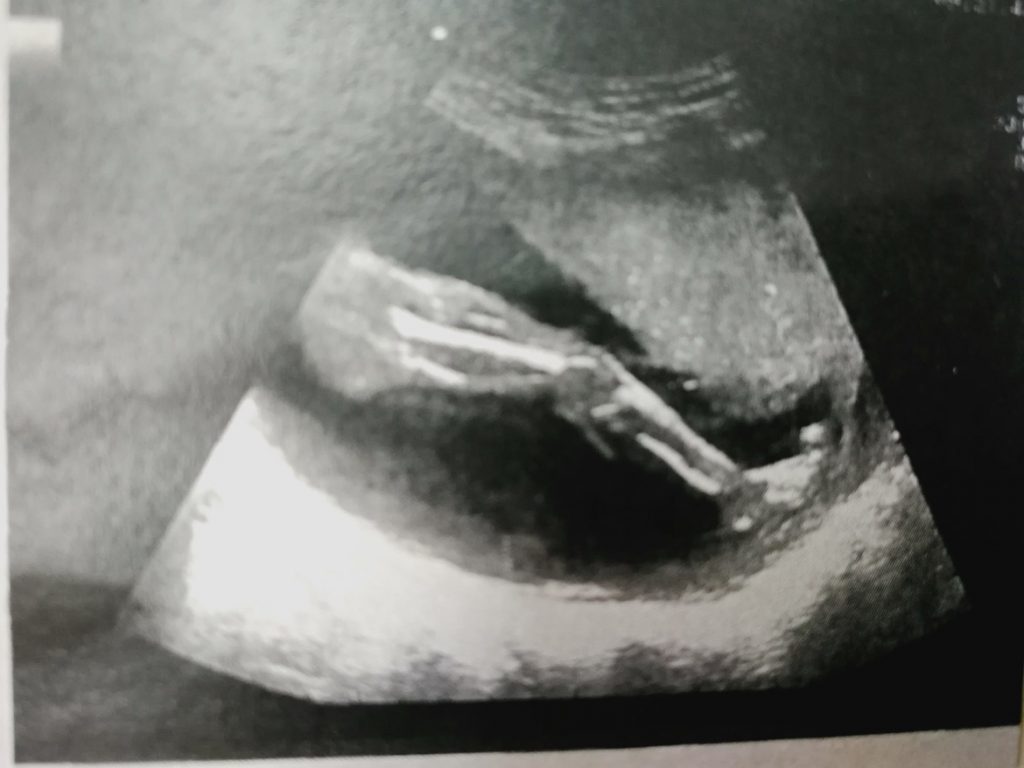

Do you remember seeing the first sonogram of your wee babe? It may not look like much to some, but to you it is proof of the utter magic that is the creation of new life. Most of us end up sharing it on social media when we announce our pregnancy, and then sticking it to the fridge where we can see its fuzzy black and white magic every time we pass. But one artist has been getting creative and turning them into beautiful, colourful paintings.

“The black and white blurry images just didn’t do my baby’s precious self, justice,” she says. “The ultrasound photographs I treasured were too small to hang on a wall, too vague to blow up and even the colours didn’t seem to do their joyful dispositions justice. It seemed a shame to tuck them away in baby books.”